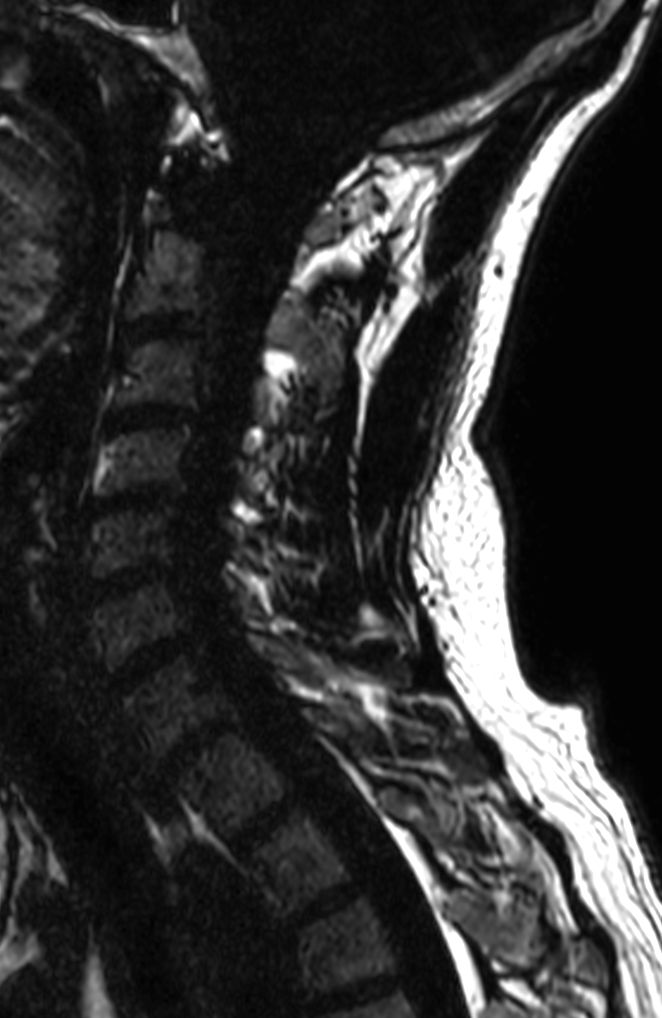

T2w TSE mDIXON XD (Water only)